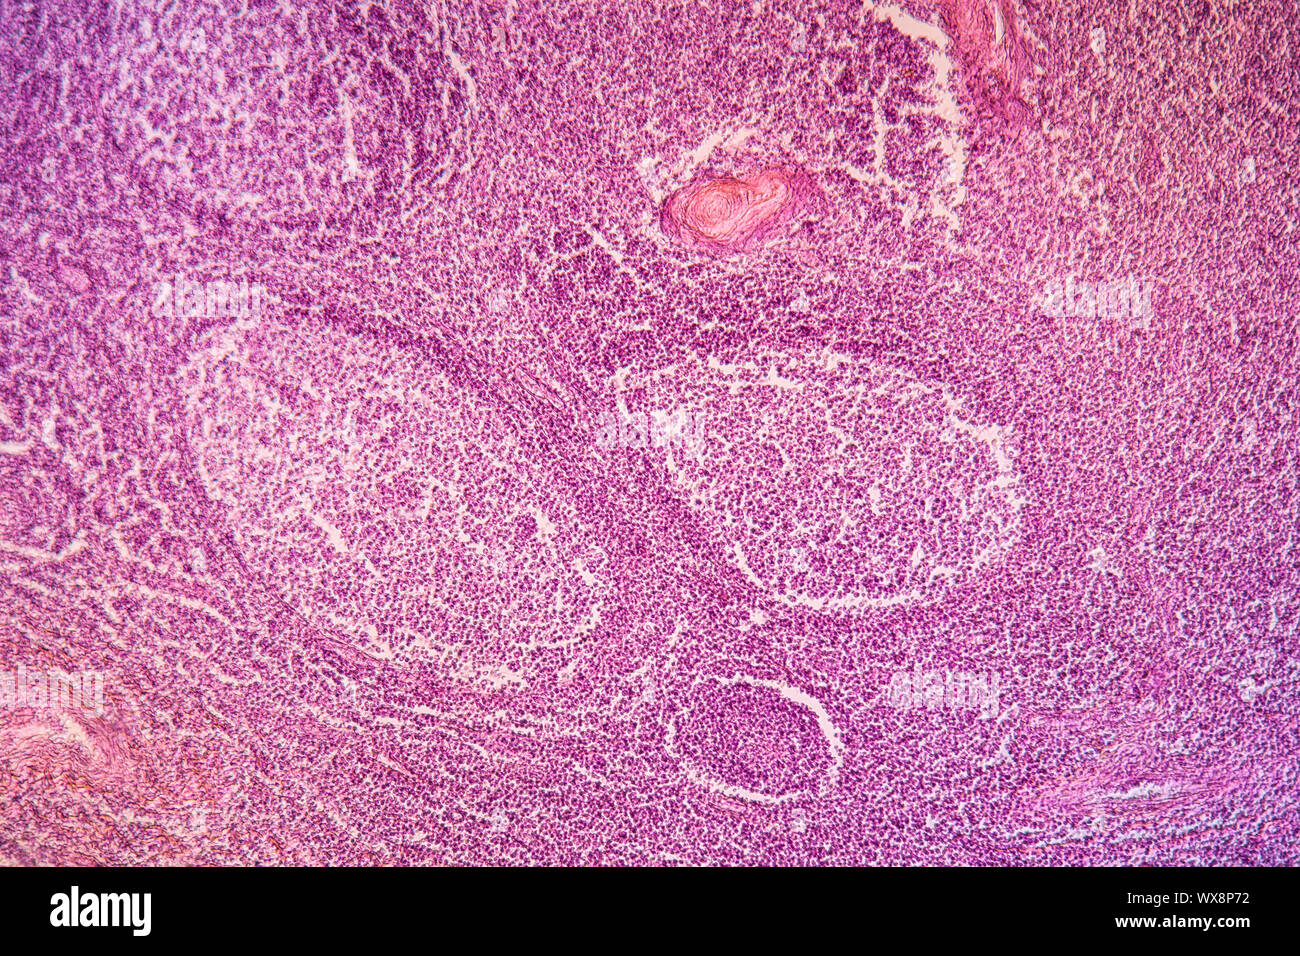

Mandelentzündung krankes Gewebe 100x Stockfotohttps://www.alamy.de/image-license-details/?v=1https://www.alamy.de/mandelentzundung-krankes-gewebe-100x-image274329575.html

Mandelentzündung krankes Gewebe 100x Stockfotohttps://www.alamy.de/image-license-details/?v=1https://www.alamy.de/mandelentzundung-krankes-gewebe-100x-image274329575.htmlRMWX8P4R–Mandelentzündung krankes Gewebe 100x